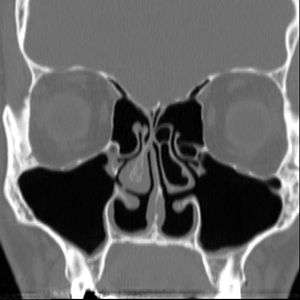

Altered nasal anatomy after bilateral subtotal inferior turbinectomy

There are no objective physical examination findings that definitely diagnose ENS.[1] Generally, one or more turbinates may be reduced or absent when viewed in medical imaging or via endoscope with no sign of physical obstruction, the mucosa will be dry and pale, and there may be signs of secondary infection.[1]